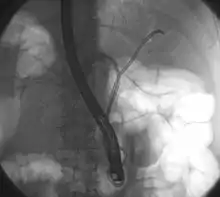

| Klatskin tumor during ERCP. Wires were inserted into the left and right biliary systems. Both parts were injected through a tube with contrast, but there is no contrast visible in the area of confluence of the two systems | |